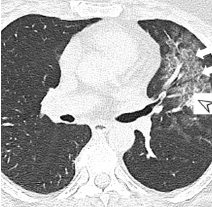

Chest